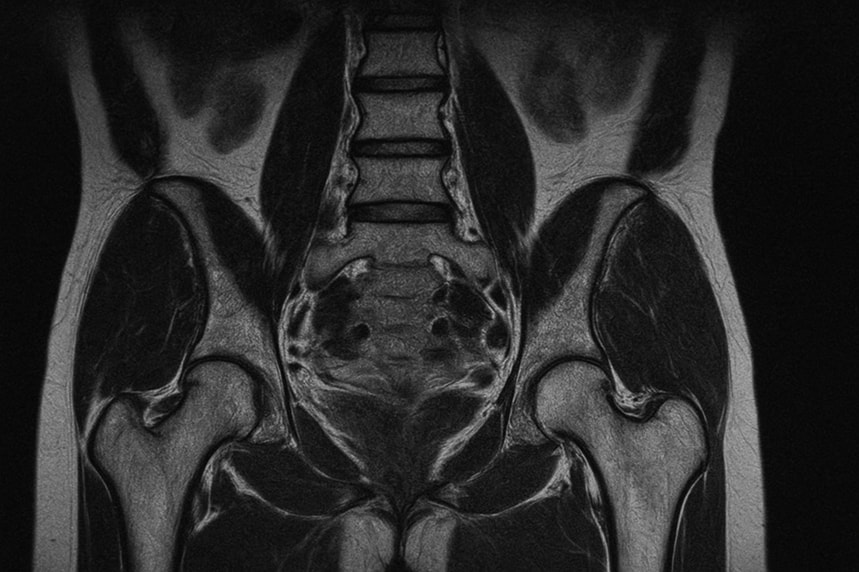

МРТ крестцово-подвздошных сочленений (КПС) — современная диагностическая процедура, позволяющая детально изучить сакроилеальные сочленения, костно-хрящевые элементы и окружающие ткани таза. Метод основан на действии сильного магнитного поля и радиоволн, создающих послойные изображения высокой четкости. Врач получает возможность увидеть структуру сустава, оценить связки, хрящевые поверхности, костный мозг и мягкие ткани в анатомическом и функциональном состоянии.

Магнитно-резонансная томография крестцово-подвздошных суставов выявляет воспалительные и дегенеративные процессы на самых ранних стадиях, когда обычные методы — рентген или УЗИ — еще не показывают отклонений. Томография позволяет диагностировать патологии крестцово-подвздошных суставов, которые часто сопровождаются болью в пояснице или крестце и ограничением подвижности. С помощью МРТ можно определить признаки воспаления, скопления жидкости, повреждение капсулы, микротрещины, а также оценить последствия травм или нагрузок.

После завершения сканирования врач-рентгенолог анализирует полученные изображения и составляет заключение. Магнитно-резонансная томография крестцово-подвздошных сочленений помогает оценить:

• наличие жидкости и воспалительных изменений в суставной полости;

• состояние хрящевой ткани и суставных поверхностей;

• отек костного мозга, эрозии, кисты;

• признаки артроза, фиброза, анкилоза;

• симметричность суставных щелей.